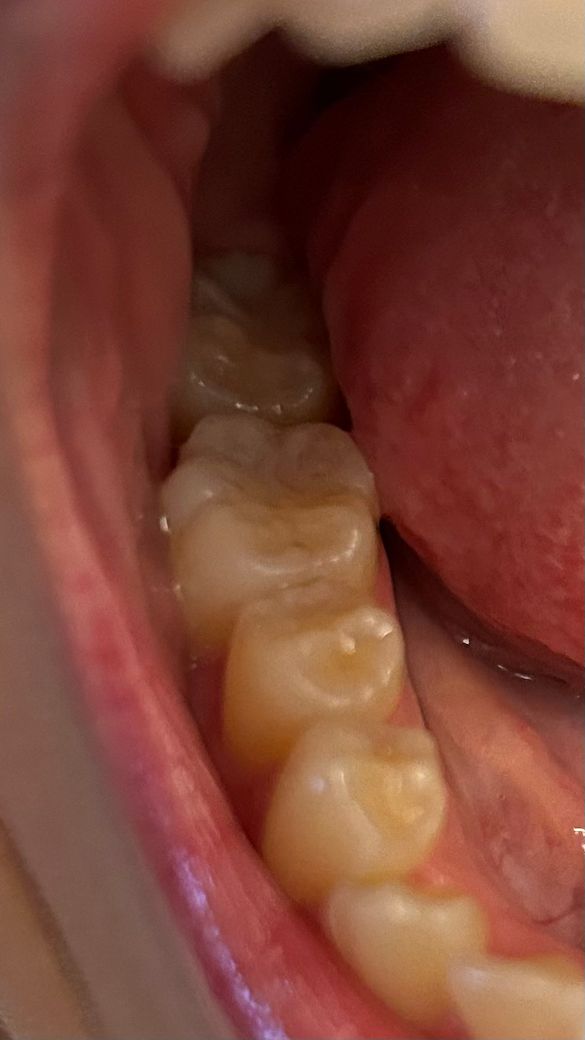

작은 충치 이 정도면 치료해야 할까요?

충치가 사진과 같이 있어요ㅠㅠ

진한 점처럼 콕 찍힌 충치도 있고 레진으로 충치 치료해놓은 곳 주변 치아 굴곡 사이에 자잘자잘하게 생긴 충치들도 보여서요ㅠ

최근에 치과 치료 갔을때 이 정도는 치료가 필요하지 않다고 듣기는 했는데 시간이 지나면서 미세하게 개수가 많아지는 것 같기도 해서 걱정이 되네요ㅠㅠ

예전에 치료를 한곳에 2차 충치가 생긴거 같습니다. 범위가 작더라도 치료를 하시는게 좋을것같습니다.

사진으로만 봤을 경우에는 특별한 치료가 필요해 보이지는 않습니다.

하지만 내부에 충치 가 진행 되어 있을수 있으니 자세한 확인을 위해 치과에서 진료를 받아보세요.